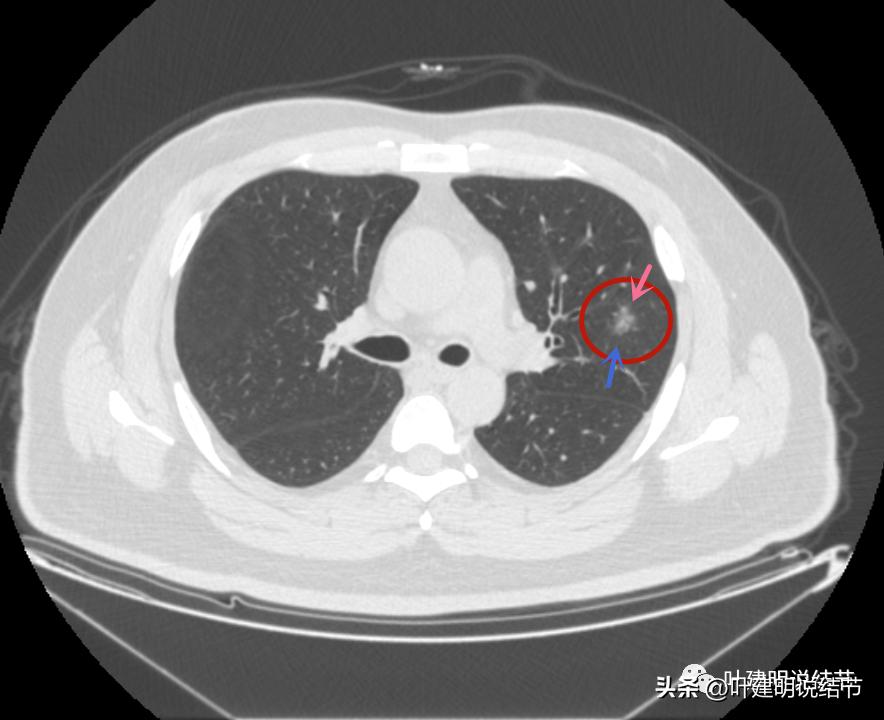

病灶3也有微血管进入(桔色箭头)

病灶3密度不均,轮廓清,有细毛刺样征(紫色箭头)

瘤现边界清

边上似乎有斑点状(绿色箭头),是不是卫星灶?

似乎有偏实性成分出现,密度较为杂乱

密度不均,瘤肺边界清,似乎是乱石征的影像

有偏实性成分,表面不平,边缘似乎有磨玻璃密度的成分

毛刺征(紫色箭头),微血管征(桔色箭头),实性点状成分(粉色箭头),整体轮廓较清(红色箭头)